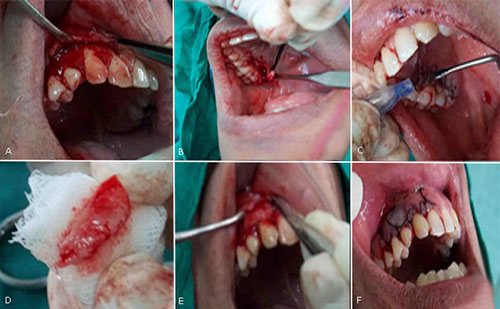

Preparación del lecho receptor: Con hoja de bisturí # 15 y mango de bisturí Bard-Parker # 3, perpendicular a la base de las papilas aledañas a los dientes involucrados, se realizó una incisión horizontal coronal a la línea amelocementaria del 13, 53 y 14. Se disecó un colgajo de espesor parcial con incisión festoneada, que se extendió 6 mm apicalmente a las recesiones del 13, 53 y 14 y en sentido mesiodistal hasta el ángulo proximal de los dientes adyacentes (de mesial del 11 a mesial del 15). Se introdujo el bisturí entre la encía y la superficie radicular a nivel de las recesiones, sin perforar la superficie vestibular del colgajo. Las papilas involucradas se desespitelizaron. Las fibras musculares se desinsertaron para dejar sin tensión al colgajo tipo bolsillo, que se diseñó del 11 al 15 con lecho perióstico firme (Fig. 2, A).

Preparación del lecho donante y obtención del injerto: Se seleccionó como sitio donador la fibromucosa palatina de distal de 15 a distal de 17. Con el bisturí mediante el abordaje de la puerta trampa a 2 mm apical al margen gingival, se separó el conjuntivo del epitelio de la mucosa masticatoria del paladar y del periostio subyacente (Fig. 2, B). Seguidamente se extrajo el injerto con pinza de disección sin dientes y se colocó en una gasa estéril impregnada de suero fisiológico. Se obtuvo un injerto de tejido conectivo de 22 mm de largo, 9,5 mm de alto y 1,6 mm de espesor. Se suturó la herida lineal resultante con sutura continua (seda negra 3-0 no reabsorbible), se usó Tisuacryl como apósito periodontal (Fig. 2, C y D).

Fijación en sitio receptor: El injerto que se obtuvo en el paso anterior, se fijó al periostio del área receptora con Tisuacryl y se cubrió con el colgajo reposicionado coronalmente (Fig. 2, D y E). Con seda negra 3-0 no reabsorbible y aguja de 3/8 de círculo con reverso cortante, se fijó la parte más coronal del colgajo con sutura suspensoria alrededor del cuello de los dientes. Se realizó sutura continua en el fondo del surco vestibular del 11 al 15 (Fig. 3, F). Se colocó cemento quirúrgico Quirucém.

Fig. 2 - A: Preparación del lecho receptor. B: Toma del injerto de zona palatina. C: Sutura de zona donante. D: Injerto de tejido conectivo. E: Fijación con Tisuacryl al periostio de zona receptora. F: Sutura del colgajo.